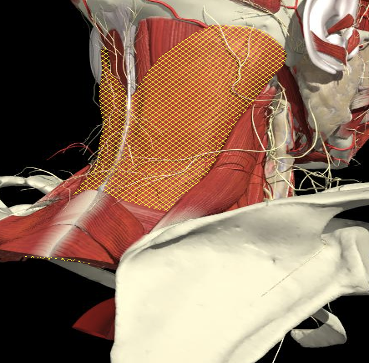

Splenius Capitis

Splenius capitis forms part of the floor of the posterior triangle of the neck, above and behind levator scapulae; it is deep to the rhomboideus and trapezius.

- Origin

- It is attached proximally to the lower half of the ligamentum nuchae, spinous processes of C7 to T4 and intervening supraspinous ligaments.

- Insertion

Action

- Individually

- Extends the head and neck, accompanied by lateral flexion of the neck and rotation of the face to the same side.

- Together

- Pure extension

Splenius Capitis/Cervicis

- Midway between the inion and mastoid process

- From the same attachment forward is SCM

- Runs obliquely to spinal processes of C7 to T3

- Cervicis runs lateral border and underneath capitus anterior to levator scapulae.